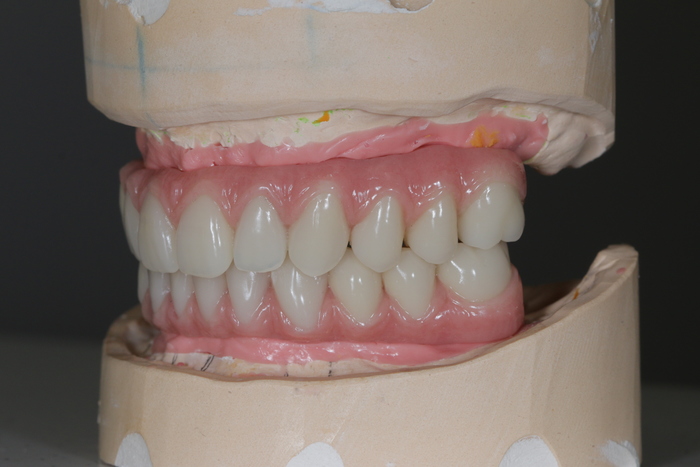

Далее ортопедом были сняты слепки, а техник в лаборатории изготовил вот такой постоянный протез с опорой на имплантатах.

И, наконец, вот так выглядит протез в полости рта